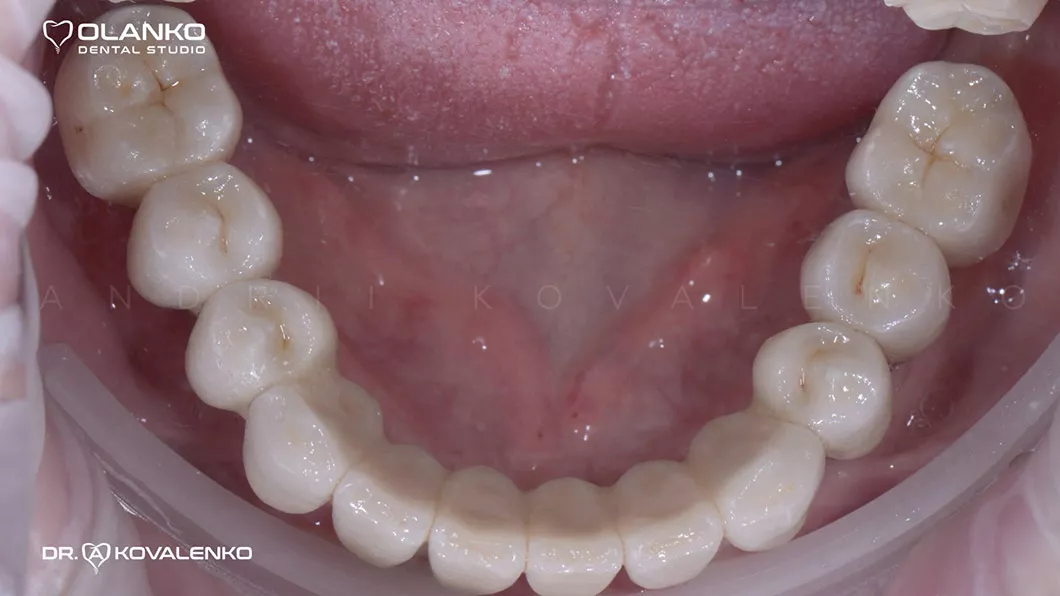

Ситуация до:

Клинический случай 1 имплантация зубов